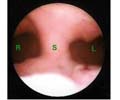

Soi BTC là phương pháp sử dụng ống soi đưa qua cổ tử cung vào buồng tử cung, làm tách thành tử cung ra để quan sát trực tiếp toàn bộ buồng tử cung, chẩn đoán và xử trí các tổn thương trong buồng tử cung.

Bằng cách nhìn trực tiếp qua soi buồng tử cung có thể quan sát được niêm mạc tử cung, xác định được các tổn thương trong buồng tử cung như dính, vách ngăn, polyp, u xơ, chẩn đoán sớm các tổn thương ung thư và tiền ung thư niêm mạc tử cung. Hơn nữa qua soi buồng tử cung có thể xử trí nhiều tổn thương bằng phẫu thuật. Phương pháp phẫu thuật qua soi buồng tử cung bảo tồn được tử cung, không có sẹo mổ ở bụng như các phương pháp phẫu thuật cổ điển qua đường bụng, thời gian nằm viện ngắn, hồi phục sau mổ nhanh.

Hình ảnh chụp Buồng tử cung trước khi phẫu thuật

-Hình ảnh buồng tử cung trên phim chụp X quang tử cung- vòi tử cung của hai nhóm vô sinh I và II khác biệt một cách có ý nghĩa thống kê.

-Phim chụp X quang tử cung- vòi tử cung thấy buồng tử cung bình thường chiếm 34,1%, trong đó nhóm vô sinh I chiếm 17,9%, nhóm vô sinh II chiếm 16,2%.

-Phim chụp X quang tử cung- vòi tử cung thấy buồng tử cung có hình khuyết chiếm 27,9%, trong đó nhóm vô sinh I chiếm 8,1%, nhóm vô sinh II chiếm 19,8%.

-Phim chụp X quang tử cung- vòi tử cung thấy buồng tử cung biến dạng chiếm 17,5%, trong đó nhóm vô sinh I chiếm 8,5%, nhóm vô sinh II chiếm 9,0%.

-Phim chụp X quang tử cung- vòi tử cung thấy buồng tử cung có bờ không đều chiếm 20,5%, trong đó nhóm vô sinh I chiếm 8,8%, nhóm vô sinh II chiếm 11,7%.